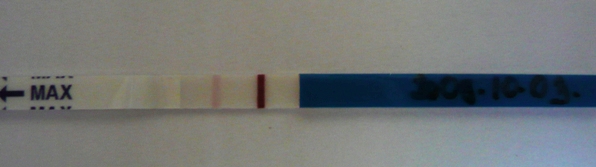

Nem hiszek a szememnek

! PRINCZIKE

ÓRIÁSI GRATULA neked

Gyönyörű a babókád! Mit éreztél a pozi teszt láttán?